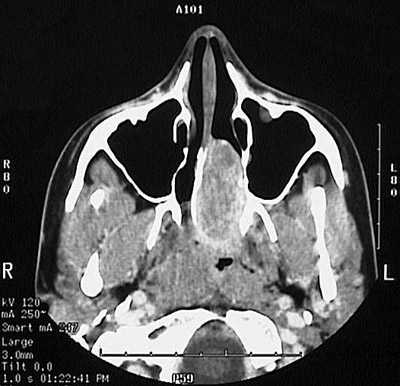

This CT scan of the head reveals an angiofibroma filling and expanding the nasal cavity on the left.